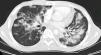

Se trata de un varón de 23 años con infección por virus de inmunodeficiencia humana (VIH) y antecedente de sarcoma de Kaposi en paladar, tratado con radioterapia y antirretrovirales hace 2 años. Consulta por la aparición de lesiones violáceas en piel de cara, disnea y dolor pleurítico con recuento de linfocitos T CD4 de 149 células/mm3 y carga viral 52.092 copias/ml. La tomografía de tórax de alta resolución (fig. 1) reveló nódulos bilaterales con bordes irregulares y áreas de vidrio esmerilado, engrosamiento peribroncovascular y derrame pleural izquierdo. La broncoscopia mostró una lesión elevada de la mucosa en segmento apical de lóbulo superior derecho y el lavado broncoalveolar (LBA), abundantes hemosiderófagos que confirman la presencia de hemorragia alveolar. La inmunohistoquímica fue positiva para herpes virus tipo 8 (VHH-8). Se inició tratamiento con doxorrubicina liposomal, y cambio de terapia antirretroviral con sobrevida de 8 meses hasta la fecha.

La tomografía de tórax revela nódulos mal definidos bilaterales y simétricos en una distribución peribroncovascular (lesiones en llama). Otros hallazgos incluyen engrosamiento septal peribroncovascular e interlobular, consolidación progresiva del espacio aéreo y opacidades en vidrio esmerilado3.